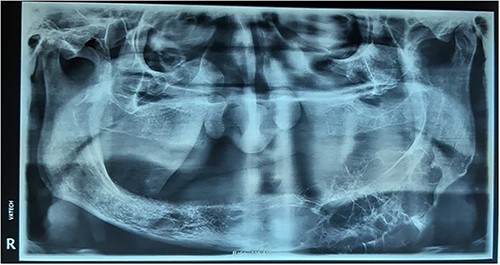

The patient was a 70-year-old man with a complaint of unilateral swelling of the face on the left side of the mandible, which occurred 4 months ago. He referred to the Faculty of Dentistry, Tehran University of Medical Sciences. On intraoral examination (Fig. 1), hard bony swelling was observed extending from the first premolar to the posterior mandible with obliteration of the vestibule. The mucosa covering this swelling was the normal mucosa of the mouth. The patient did not report a history of significant systemic disease. In the orthopantomograph image, irregular multilocular radiolucency was observed, with distinct septa from the anterior mandible extending distally to the ramus (Fig. 2). Perforation of the lower mandibular cortex was also visible in some areas. Computed tomography (CT) showed a Hypodense osteolytic lesion on the left side of the mandible, extending from the anterior region to the molar region. CT image also showed buccolingual expansion and cortical perforation on the buccal and lingual side, indicating a locally aggressive lesion.

Panoramic view showing irregular multilocular radiolucency from the anterior mandible extending distally to the ramus.